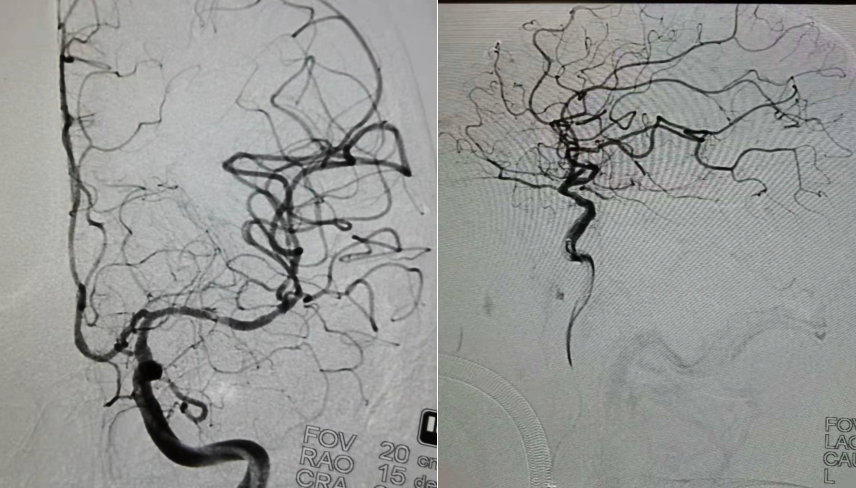

拉栓后复查造影,血管通畅

这是一例大核心梗死超时间窗急性AIS病人中间导管抽吸联合支架取栓病例。患者最后正常时间距离就诊时间约7.5小时。目前对于超时间窗急性脑梗死患者血管再通治疗指征,组织窗及灌注检查非常重要,通过灌注检查可以判断是否存在大面积低灌注区域并及时恢复血流,成为血管再通治疗是否获益的关键。经术前颅脑CT、MRI及DWI评估,提示左侧脑组织大范围核心梗死,DWI及FLAIR明显不匹配,如果取栓血管再通后,能挽救部分缺血半暗带,但再通后脑组织高灌注水肿、出血风险较大,应充分认识到取栓术后短时间内二次手术去骨瓣减压可能性较大。对于大梗死核心的取栓手术指南没有明确推荐,但有部分病人手术后明显获益。该患者年轻,家属积极,术前充分与患者家属沟通,机械取栓及去骨瓣手术协议书一并签署。本例患者颈内动脉末端急性闭塞,易形成大负荷量血栓,单纯支架取栓容易造成血栓逃逸,造成远端血管栓塞。先使用心玮Extraflex远端通路导管抽吸,再使用SWIM技术拉栓及抽吸同步进行,可以有效避免该情况发生。术中支架拉出绿豆粒大小血栓,中间导管抽吸出血栓碎屑。心玮Extraflex远端通路导管抽吸力大,通过性和稳定性都让人眼前一亮。